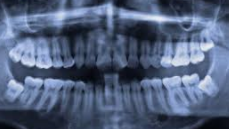

사람의 턱은 크기가 한정되어 있기 때문에 수용할 수 있는 치아의 갯수가 한정적입니다. 턱이 발달되고 큰 사람들은 사랑니가 자라나도 정상적으로 자라나 문제가 없을수도 있지만 사랑니가 자라는 대부분의 사람들은 수용할 수 있는 치아의 갯수가 초과되기 때문에 치아가 자라날 자리가 없어 잇몸을 비집고 자라거나 잇몸안에서 나오지 못하는 경우가 대부분 입니다.